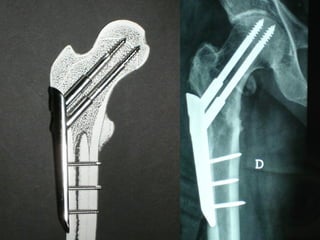

The GOTFRIED plate

La placca a compressione percutanea (PC.C.P.) di Gotfried è un mezzo di sintesi studiato per assicurare un “impattamento controllato” delle fratture pertrocanteriche grazie alle due viti telescopiche prossimali che garantiscono una ottima stabilità rotazionale

Con la placca di Gotfried non si è mai riscontrato un danno iatrogeno del muro laterale e nessun collasso della frattura.Ciò è dovuto al fatto che i fori per l’applicazione delle due viti prossimali sono di piccolo diametro (9 mm) rispetto ai 16-32 mm necessari per introdurre la vite cefalica di un chiodo endomidollare o di una vite-placca a compressione.

La placca PC.C.P. viene inoltre applicata per via percutanea attraverso due piccole incisioni ottenendo in tal modo un minimo trauma chirurgico ed una  perdita di sangue estremamente ridotta in pazienti che per l’età  sono già in condizioni  critiche